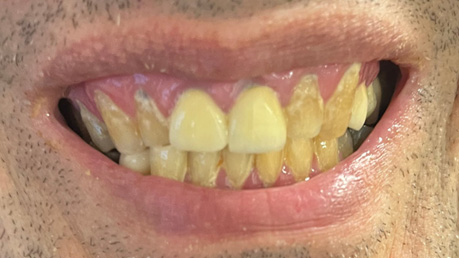

Patient Intraoral Photographs

- Frontal view